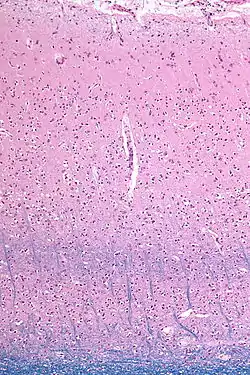

![]() Micrograph showing the visual cortex (predominantly pink). The blue, horizontal band in the lower half of the image are the bands of Baillarger/the line of Gennari. Subcortical white matter (predominantly blue) is seen at the very bottom of the image. LFB stain. | |